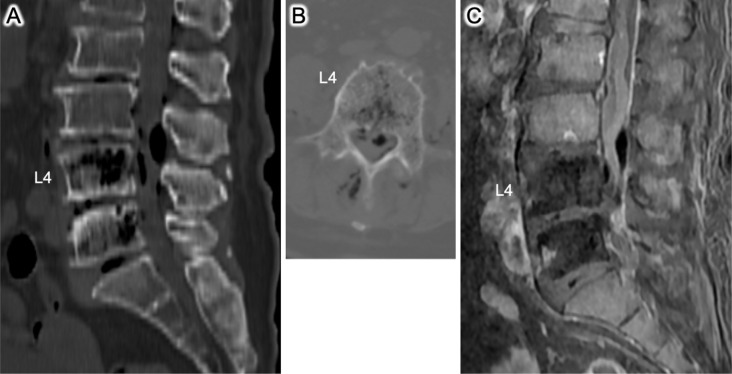

Abstract Image